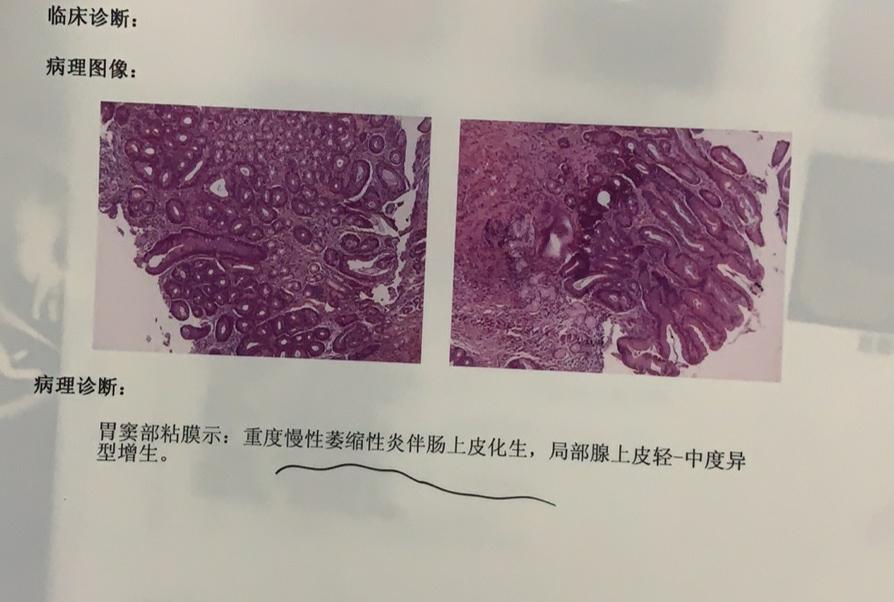

胃窦活检

2014-02-17 方占和 医师 最近胃有点不舒服,胃镜活检报告显示(胃窦)

胃窦部黏膜组织活检镜下如图所示胃黏膜发生的有关病变的描述

胃窦部黏膜组织活检镜下如图所示胃黏膜发生的有关病变的描述错误的是

胃窦部黏膜活检

胃窦活检

胃窦部黏膜活检

胃窦部黏膜活检

胃窦部黏膜活检